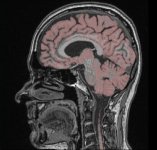

Screenshots

|

|

|

| YaDiV Hauptfenster | Region of Interest | Segmentierung |

|

|

|

| 2D Segmentvisualierung | 3D Segmentvisualierung | Marching Cube |